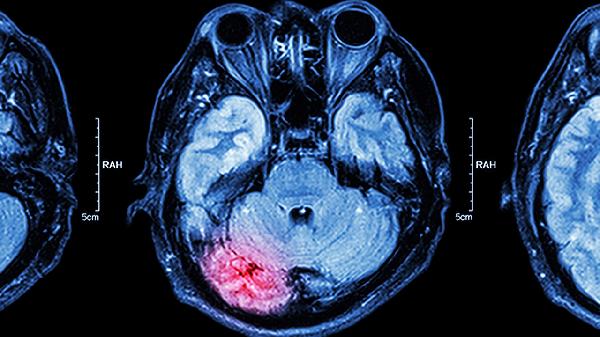

病毒性脑炎是一种由多种病毒引起的颅内感染,常见的病原体包括单纯疱疹病毒、肠道病毒、虫媒病毒、麻疹病毒和EB病毒等。这些病毒主要通过呼吸道、消化道、蚊虫叮咬、直接接触以及母婴垂直传播等方式进入人体。